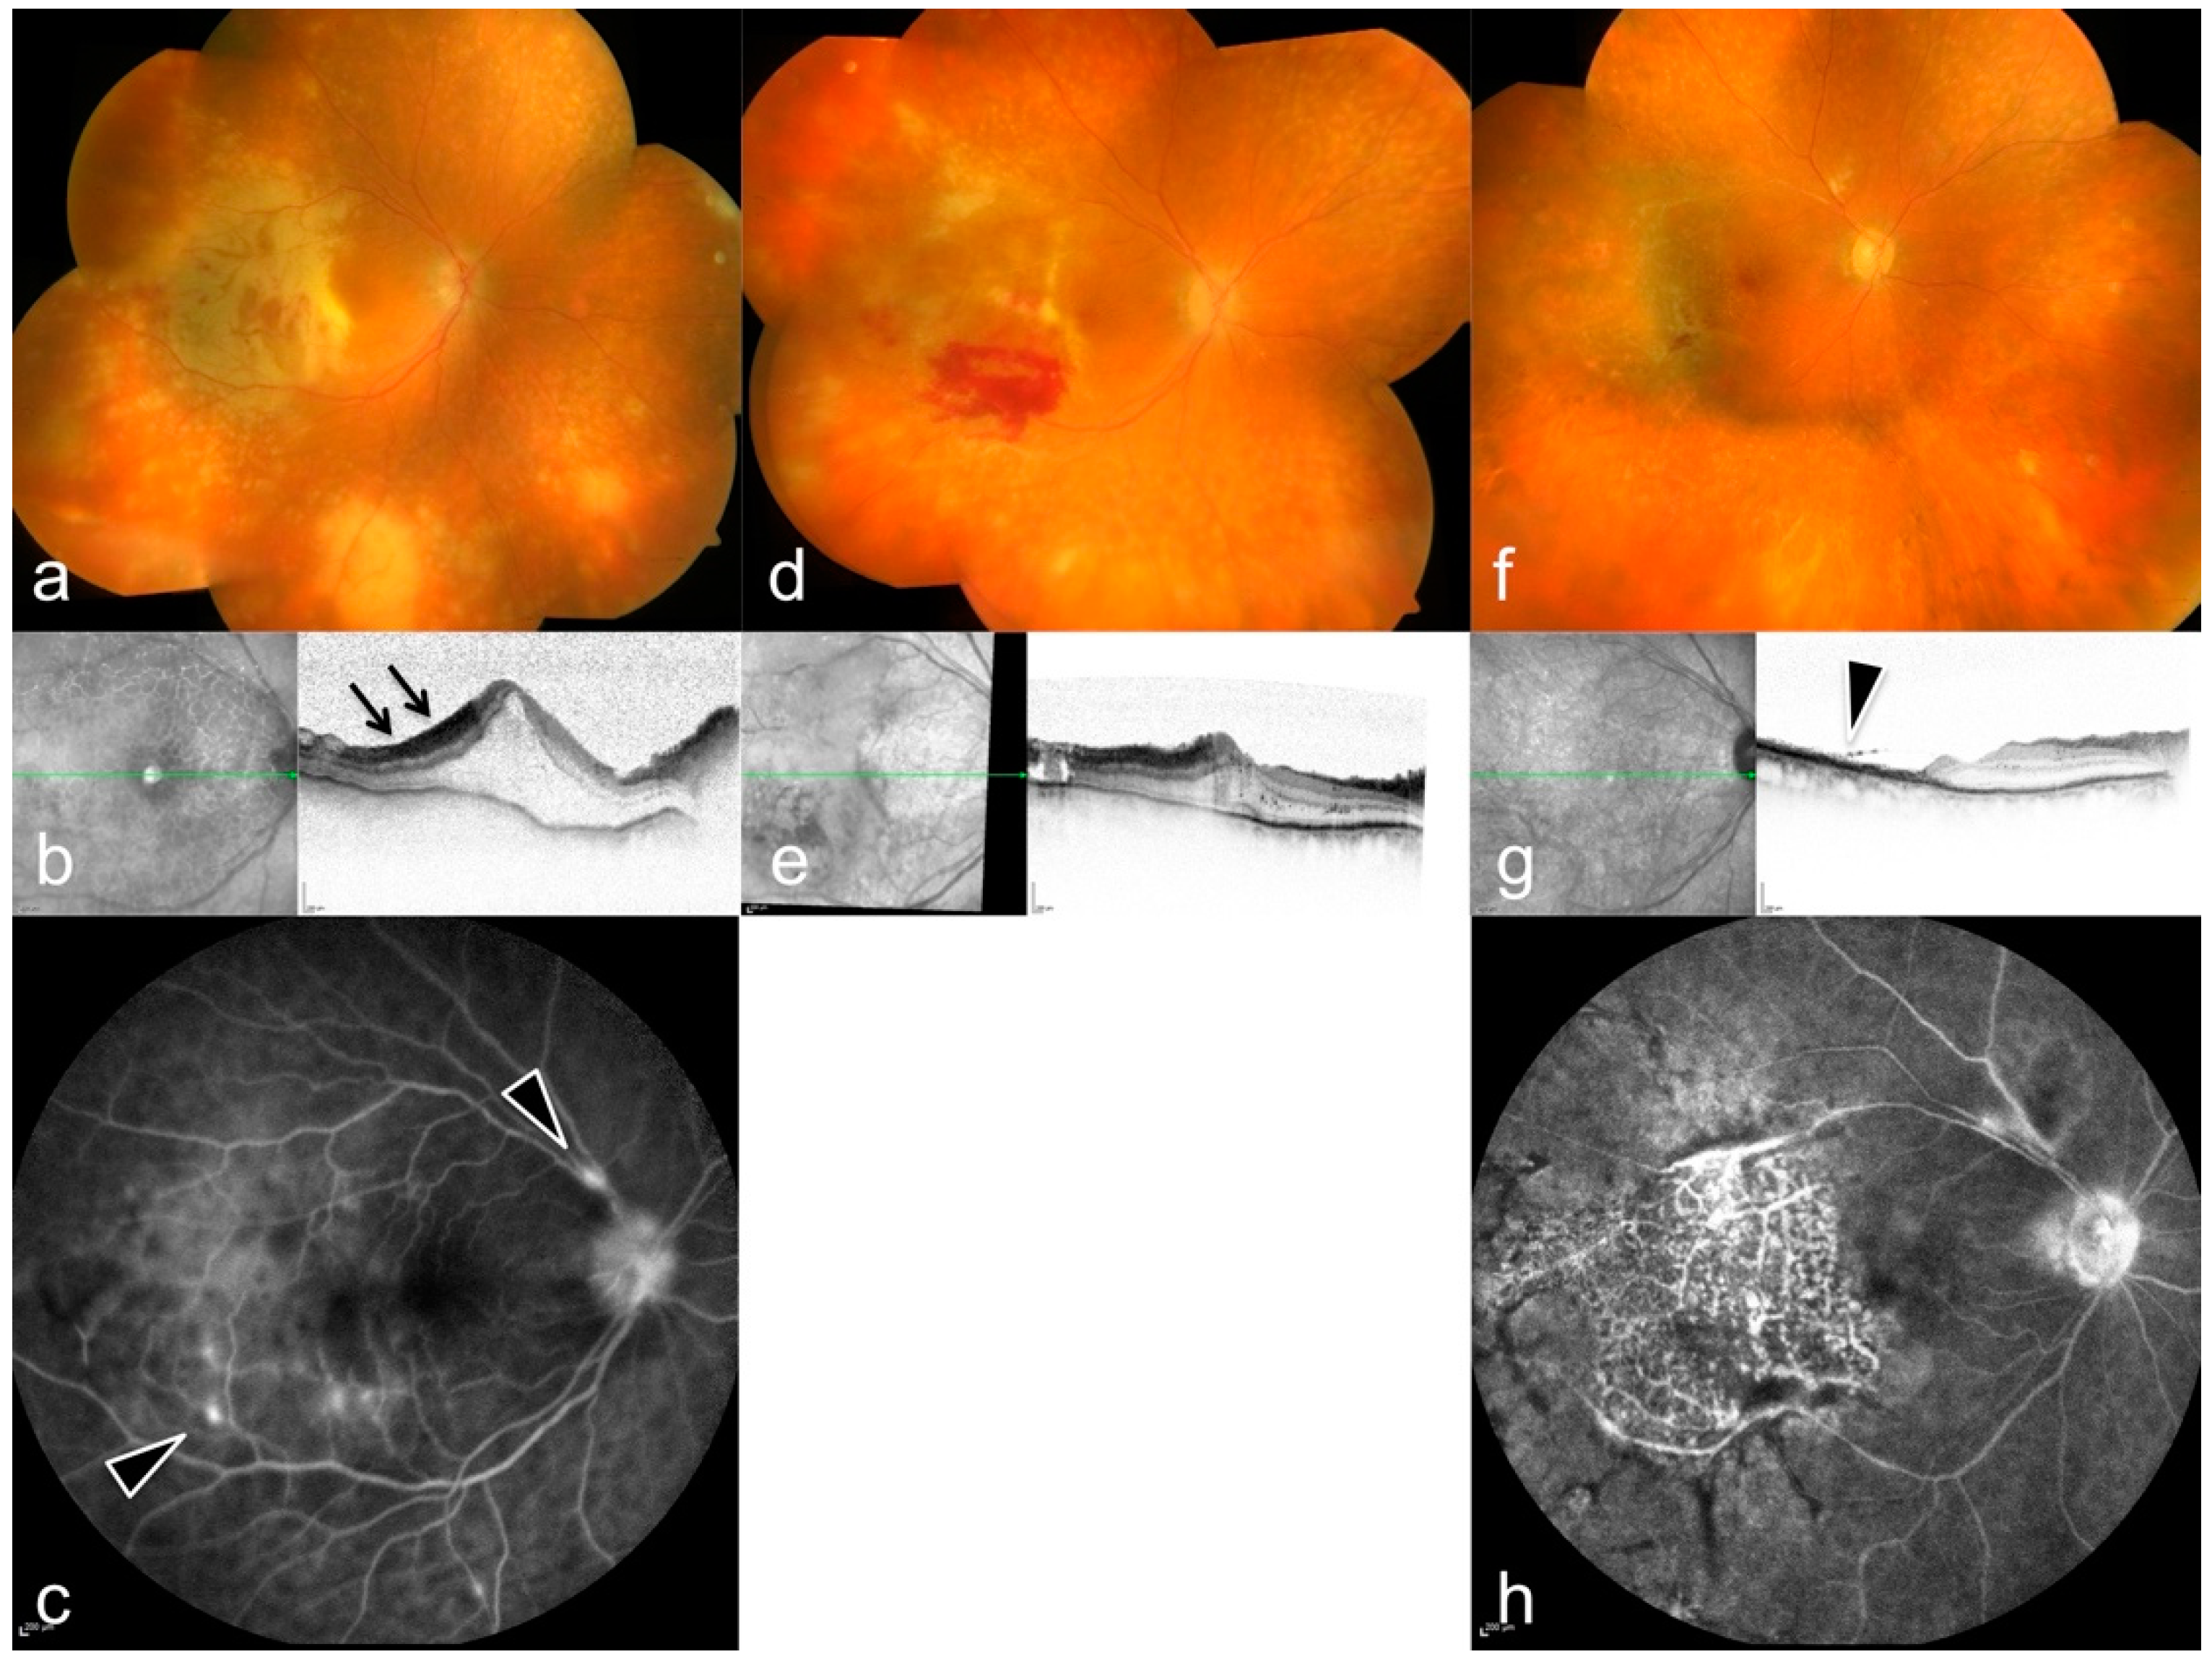

Acute Retinal Necrosis: Signs, Treatment, Complications and Outcome

3. Results